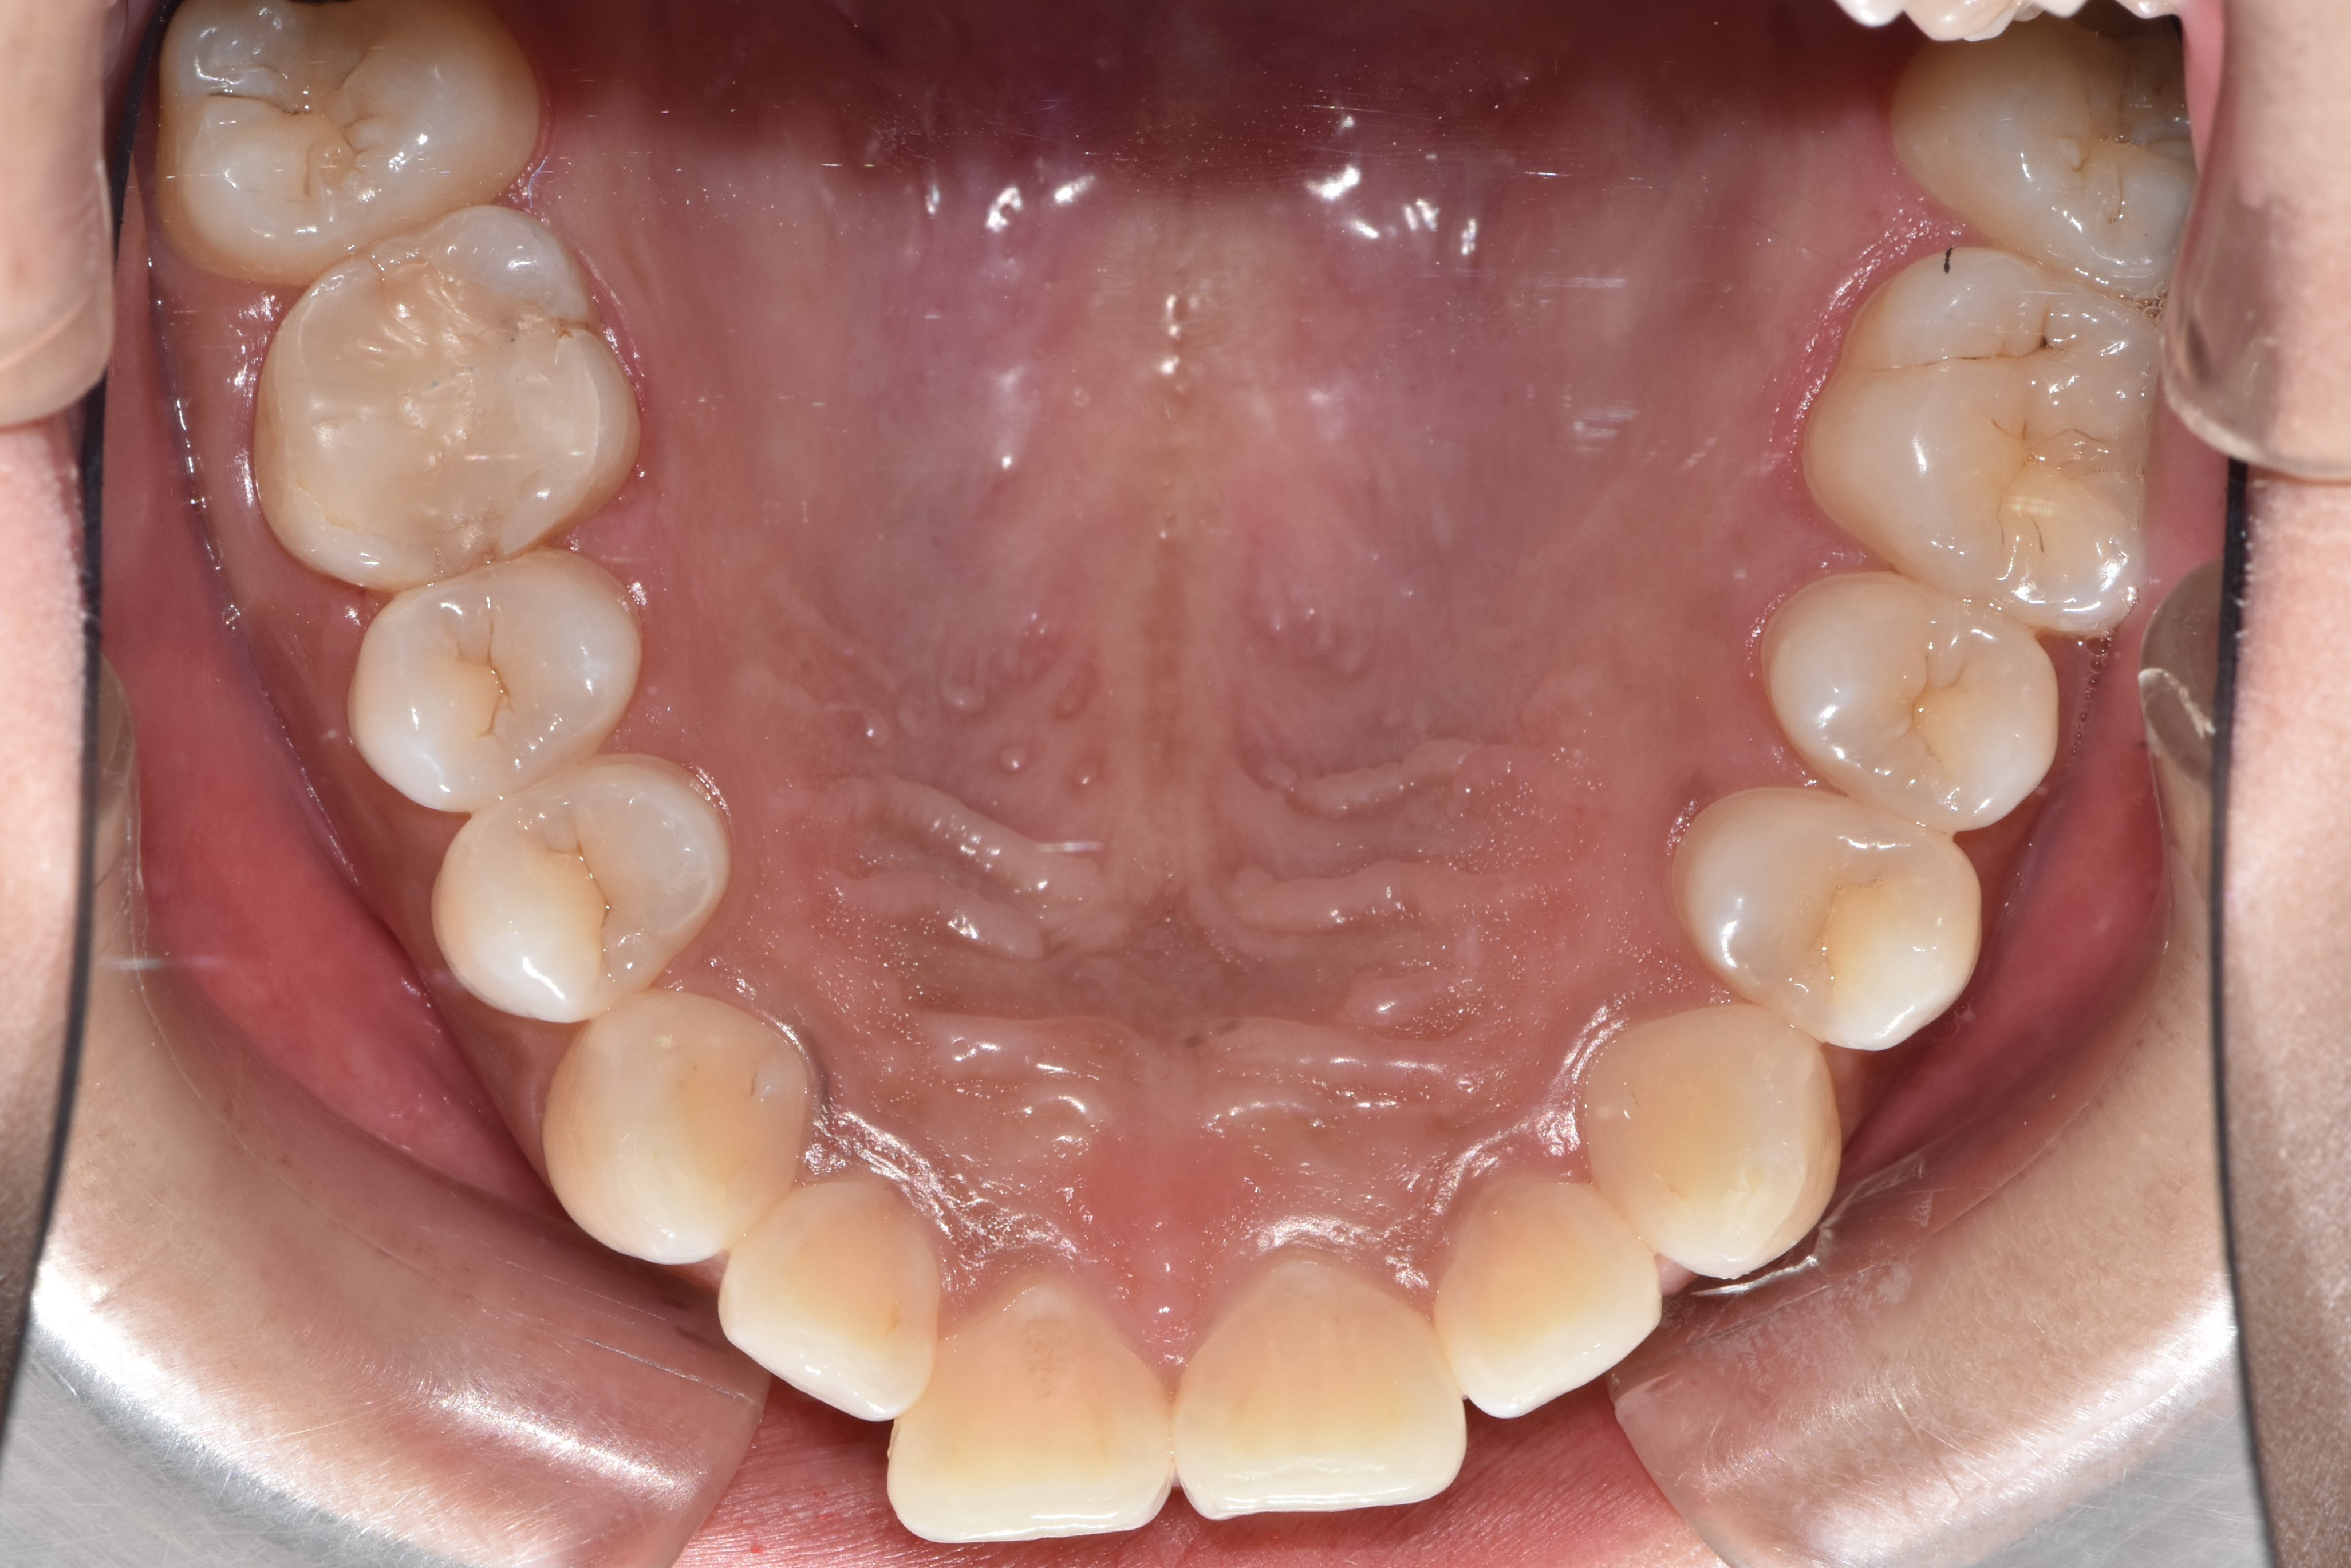

디테일한 치아 조절이 어렵다보니, 치아가 가지런하게 배열은 되지만, 가까이 들여다보면 치아배열이 조금 비뚤 수 있다.

한 가지 아이러니한 상황이 생기는데, 투명교정은 부정교합이 심하지 않은 부분교정 환자에서 많이 사용하는데,

마지막에 이런 미세한 부분은 고치지 못하게 되니 불만족스러워하는 환자들이 꽤 발생한다.